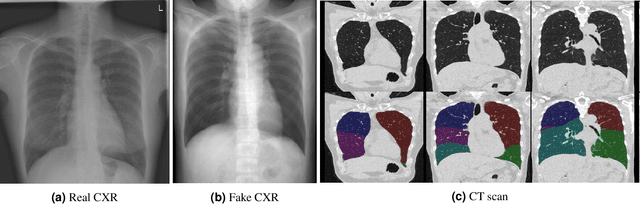

Abstract:Total lung volume is an important quantitative biomarker and is used for the assessment of restrictive lung diseases. In this study, we investigate the performance of several deep-learning approaches for automated measurement of total lung volume from chest radiographs. 7621 posteroanterior and lateral view chest radiographs (CXR) were collected from patients with chest CT available. Similarly, 928 CXR studies were chosen from patients with pulmonary function test (PFT) results. The reference total lung volume was calculated from lung segmentation on CT or PFT data, respectively. This dataset was used to train deep-learning architectures to predict total lung volume from chest radiographs. The experiments were constructed in a step-wise fashion with increasing complexity to demonstrate the effect of training with CT-derived labels only and the sources of error. The optimal models were tested on 291 CXR studies with reference lung volume obtained from PFT. The optimal deep-learning regression model showed an MAE of 408 ml and a MAPE of 8.1\% and Pearson's r = 0.92 using both frontal and lateral chest radiographs as input. CT-derived labels were useful for pre-training but the optimal performance was obtained by fine-tuning the network with PFT-derived labels. We demonstrate, for the first time, that state-of-the-art deep learning solutions can accurately measure total lung volume from plain chest radiographs. The proposed model can be used to obtain total lung volume from routinely acquired chest radiographs at no additional cost and could be a useful tool to identify trends over time in patients referred regularly for chest x-rays.

Abstract:Amidst the ongoing pandemic, several studies have shown that COVID-19 classification and grading using computed tomography (CT) images can be automated with convolutional neural networks (CNNs). Many of these studies focused on reporting initial results of algorithms that were assembled from commonly used components. The choice of these components was often pragmatic rather than systematic. For instance, several studies used 2D CNNs even though these might not be optimal for handling 3D CT volumes. This paper identifies a variety of components that increase the performance of CNN-based algorithms for COVID-19 grading from CT images. We investigated the effectiveness of using a 3D CNN instead of a 2D CNN, of using transfer learning to initialize the network, of providing automatically computed lesion maps as additional network input, and of predicting a continuous instead of a categorical output. A 3D CNN with these components achieved an area under the ROC curve (AUC) of 0.934 on our test set of 105 CT scans and an AUC of 0.923 on a publicly available set of 742 CT scans, a substantial improvement in comparison with a previously published 2D CNN. An ablation study demonstrated that in addition to using a 3D CNN instead of a 2D CNN transfer learning contributed the most and continuous output contributed the least to improving the model performance.